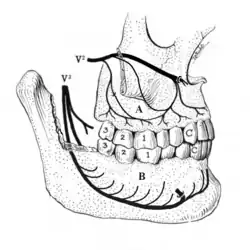

A tooth is composed of an outer shell of calcified hard tissues (from hardest to softest: enamel, dentin, and cementum), and an inner soft tissue core (the pulp system), which contains nerves and blood vessels. The visible parts of the teeth in the mouth – the crowns (covered by enamel) – are anchored into the bone by the roots (covered by cementum). Underneath the cementum and enamel layers, dentin forms the bulk of the tooth and surrounds the pulp system. The part of the pulp inside the crown is the pulp chamber, and the central soft tissue nutrient canals within each root are root canals, exiting through one or more holes at the root end (apical foramen/foramina). The periodontal ligament connects the roots to the bony socket. The gingiva covers the alveolar processes, the tooth-bearing arches of the jaws.[42]: 1–5